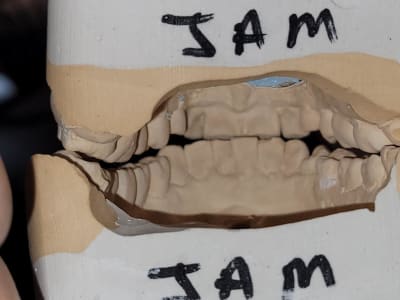

je reçois cette patiente de 70 ans pour une fracture de la 28. Je l'avais vu en 2016 pour une réfection de son bridge secteur 3. Quand je lui demande de serrer voici ce que je trouve. Je ne comprends pas bien ce qu'il s'est passé... Quand je l'interroge, elle me dit qu'elle éprouve des difficultés à la mastication depuis 3 mois avec problèmes de morsure à gauche. Au début je pensais qu'avec extraction des DS et réfections des couronnes sur les 7 a droite cela pourrait passer mais les prémo su se sont versées en palatin. Bref je mouline !

ce que tu nous montres là , c est la position de fermeture telle que tu l as vu au fauteuil ? je suppose .

Je fais suite avec l'OIM que je trouve. a priori, Déviation a gauche. Serait ce pour repositionner L'atm droite ou pour éviter une gêne a droite ? (en rouge rapport sur articu )